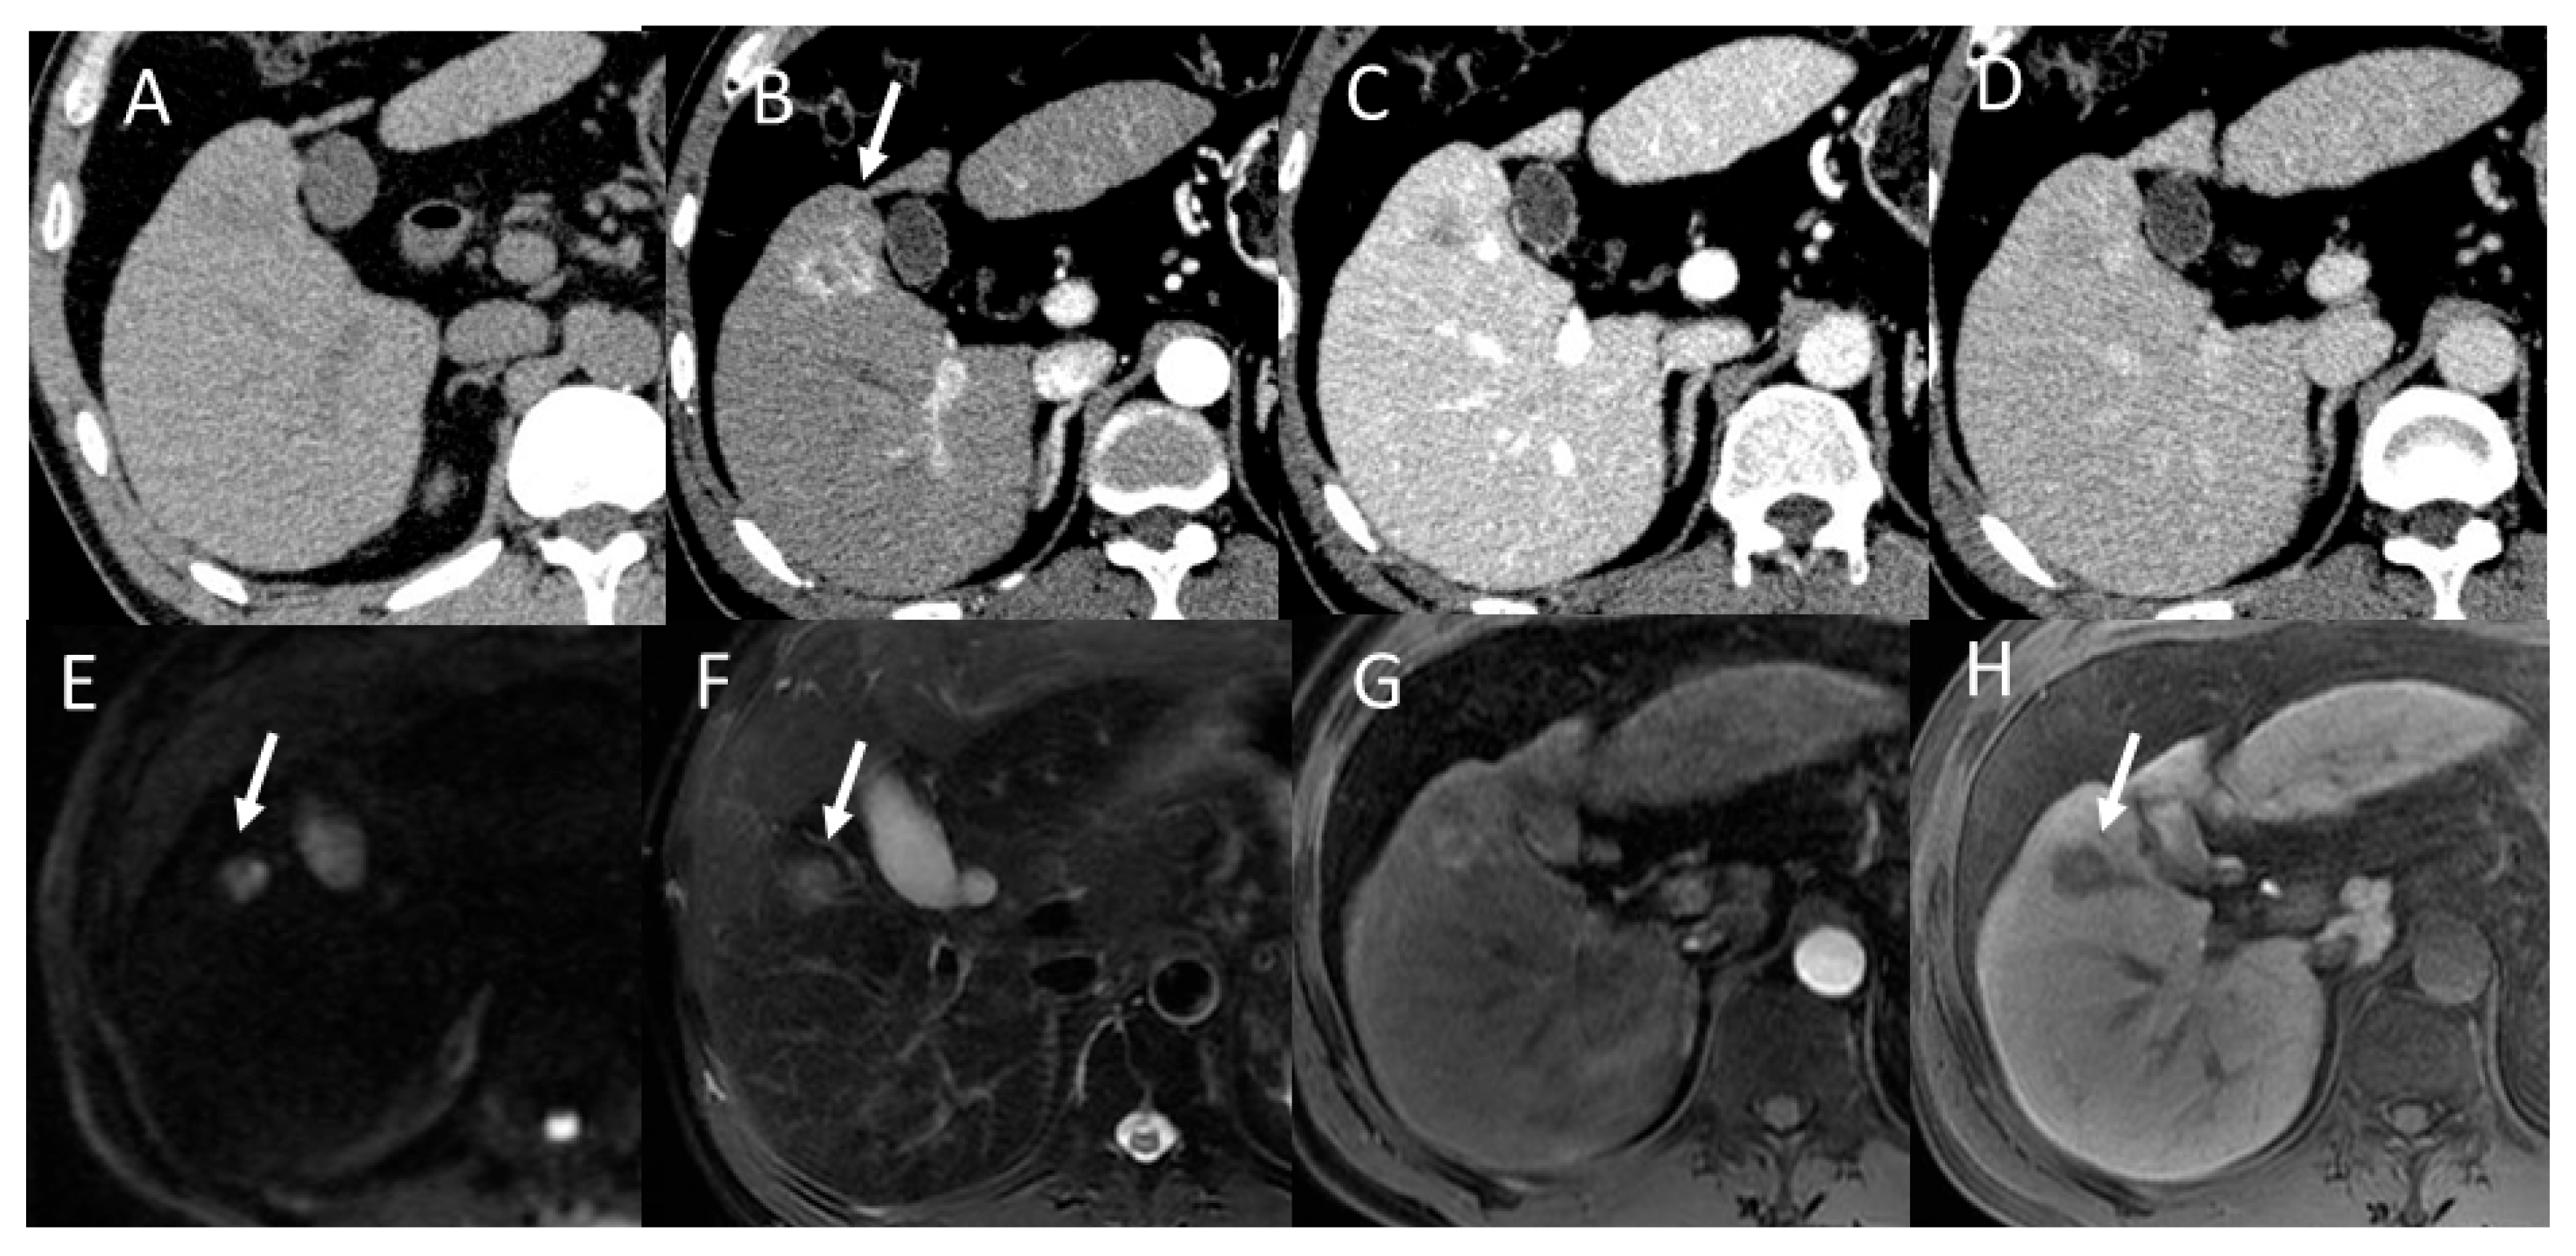

4.8. Steatohepatitic HCC (SH-HCC)